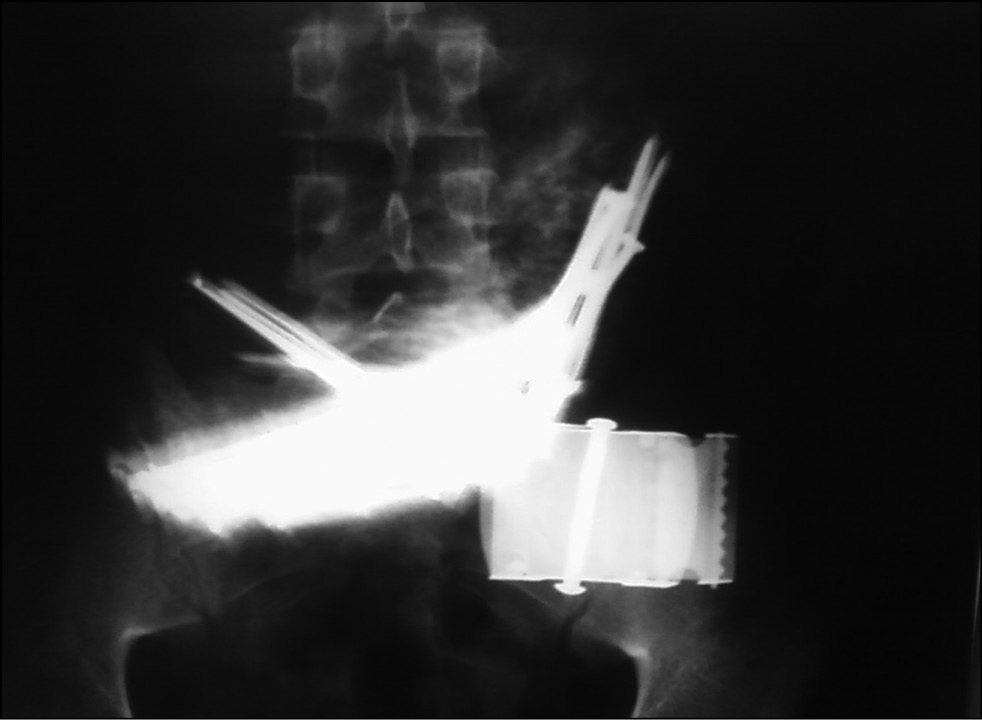

X-ray imaging data of the abdominal cavity on August 15, 2011, was as follows: “200 mL of barium solution was given per-os: foreign bodies ≈20 pieces ~ 15 cm long nails are located in the stomach” (Figs. 1 and 2).

Fig. 1. X-ray of the abdomen (front projection — military uniform).

Fig. 2. X-ray of the abdomen (front projection).